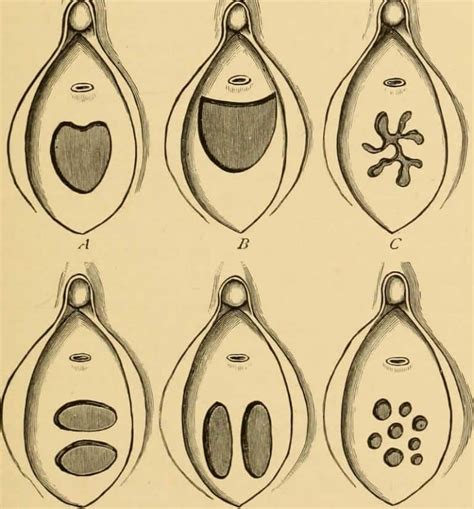

Bozulmuş Kızlık Zarı Hakkında Kısa Bilgi Bozulmuş kızlık zarı belirtileri, birçok kadının merak ettiği konular...